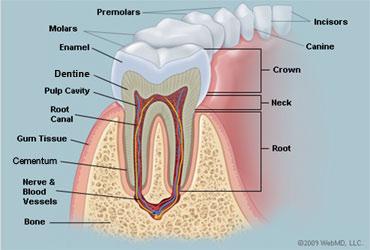

10

Rugae of the Hard Palate

11

Vestibule

12

Uvula

13

Deciduous Teeth

baby teeth

14

Permanent Teeth

15

Incisors (8)

Permanent Teeth FRONT

16

Canines (4)

Permanent Teeth

17

Premolars (8)

Permanent Teeth

18

Molars (12)

Permanent Teeth

19

Crown

20

Neck

21

Root

22

Alveoli

23

Gingiva

24

Enamel

25

Dentin

26

Cementum

27